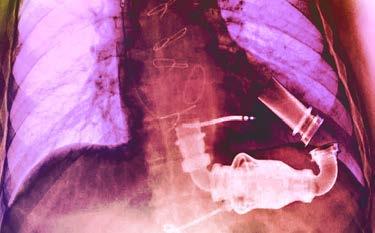

LVADs, the implanted mechanical pumps that help the bottom left chamber of a failing heart move blood to the aorta, the body’s main artery, and then throughout the body, are an example.

First used in the mid1960s, the devices were once so large that they were only used in hospitals for short-term support.

Their size also meant that women were mostly excluded from being able to use an LVAD, says Wendy Book, director of the Emory Adult Congenital Heart Center. “Now they are so small they fit in the palm of your hand. In fact, they have been miniaturized enough that babies and children with heart defects who need transplants can benefit from these devices.”

Durable LVADs designed for long-term implantation are not only helping patients awaiting heart transplants, they also are used to improve heart function in people with advanced heart failure who aren’t candidates for transplant.